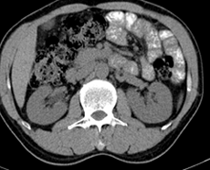

患者,男,57,常年不吃午饭,近一个月来腹部隐痛,无明显黄疸,明天进行增强扫描,图象另上传,麻烦各位帮忙一起看看讨论讨论

肝外胆管扩张,胰头增大,肠系膜上静脉似有包埋征象。

考虑:胰头占位性病变,建议增强进一步检查。

肝外胆管稍扩张,胰腺钩突略增大,但外形尚可,境界清楚。(常年不吃午饭)提示胰腺炎可能大,肿瘤第二步考虑。

支持考胰头占位性病变,感觉十二指肠壁不规则增厚,不排除十二指肠降部占位可炎症

胰头增大,胆总管增宽,考虑胰头癌可能性大,明天看增强片有助诊断.